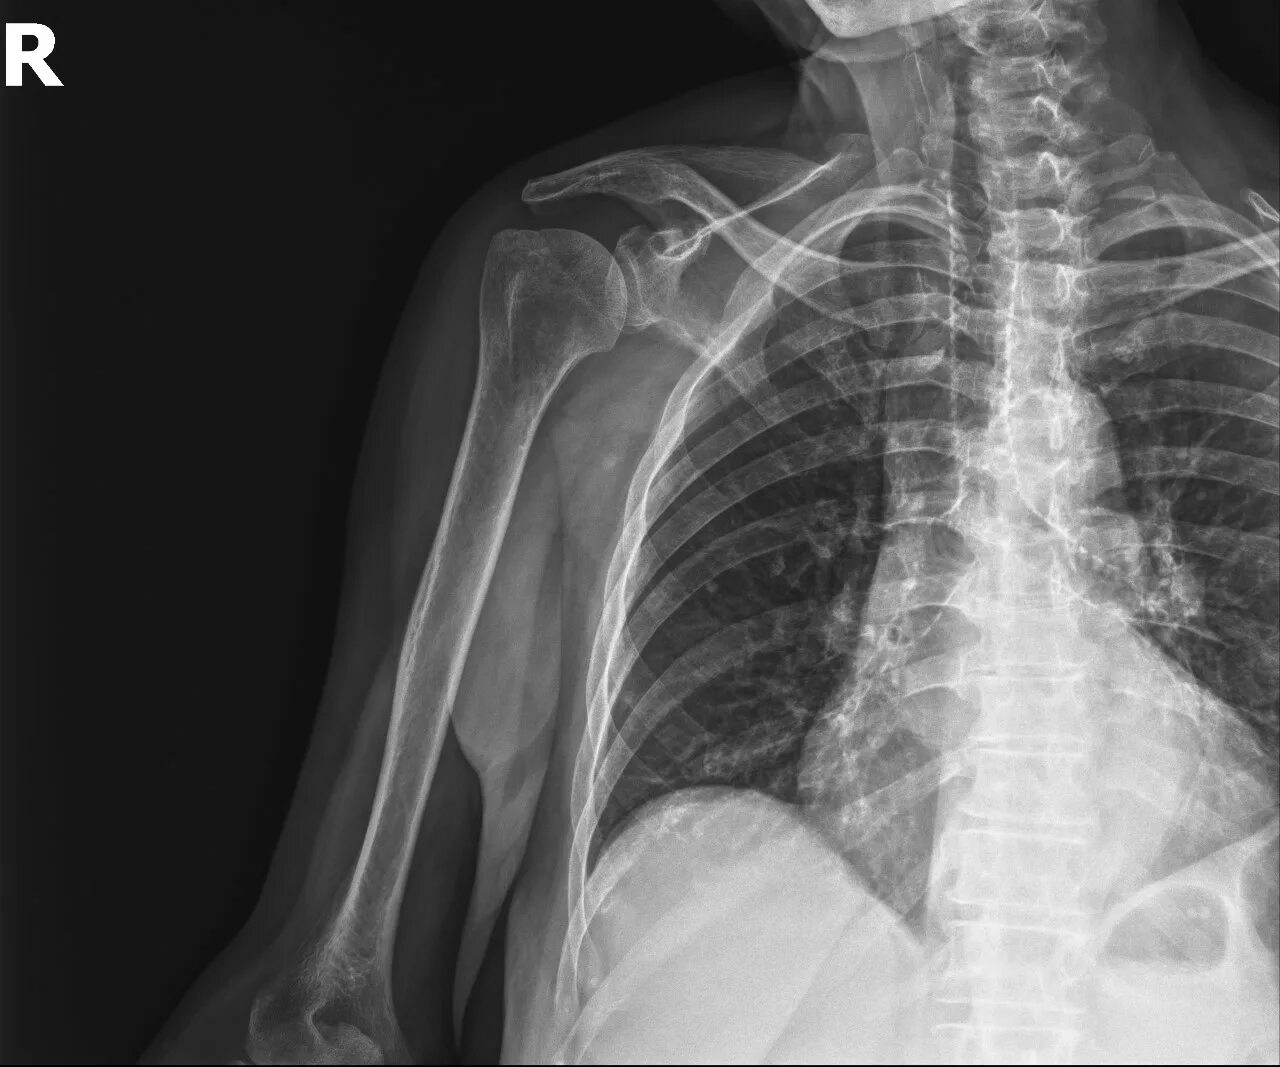

Перелом б бугорка